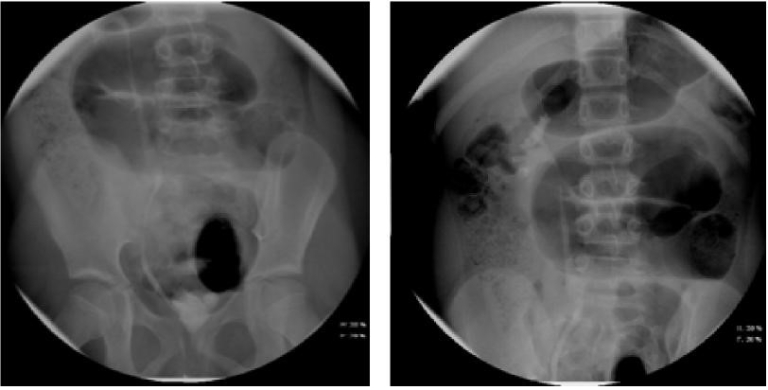

- Voiding Cystourethrogram (VCUG) (Figures 1 and 3) A VCUG is helpful in identifying bladder emptying, vesicoureteral reflux (VUR) or urethral obstruction. It should not be obtained until after a child is afebrile for at least 24 hours and is no longer symptomatic. It should be obtained in children less than 2 months with a febrile UTI, in the setting of abnormal anatomy on RBUS (hydronephrosis, renal scarring, etc.), or in other atypical or complex situations. It should be obtained in children 2 to 24 months following a second febrile UTI.6, 7